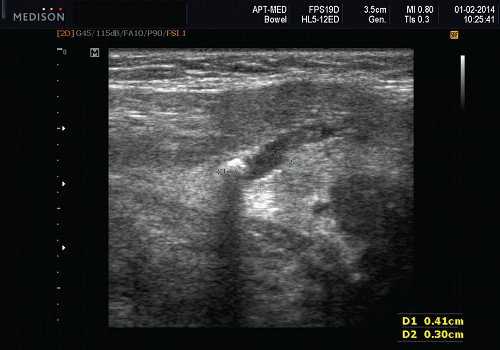

- Необычная кальцификация, наблюдаемая на ультрасонографии при наличии давно существующей опухоли.

- Наличие кальциноза в доброкачественной смешанной опухоли подчелюстной железы указывает на давнюю опухоль и должно вызывать подозрение.

Серошкальное УЗИ. Хорошо выраженная, солидная и гипоэхогенная по сравнению с прилегающей тканью слюны. Однородная внутренняя эхо-структура с задним акустическим усилением. Опухоль имеет несколько тканевых границ и позволяет звуку легко проникать, вызывая улучшение заднего отдела. Большие опухоли могут иметь неоднородные внутренние эхосигналы из-за кровоизлияния и некроза. Гетерогенная плеоморфная аденома может иметь нечеткие границы, имитирующие злокачественную опухоль. Большие опухоли могут иметь дольки и появляться на ножке. Необычный кальциноз при ультразвуковом сканировании наблюдается при давней опухоли. Кожа и подкожные ткани в норме

Оценивая опухоль слюнной железы, внимательно оценивайте ее характеристики. Край: злокачественные опухоли имеют нечеткие края по сравнению с доброкачественными образованиями. Внутренняя архитектура: злокачественные опухоли имеют неоднородную архитектуру; доброкачественные опухоли обычно имеют однородную архитектуру. Злокачественные опухоли, более вероятно, связаны с внежелезистой инфильтрацией и поражением узлов. Злокачественные опухоли чаще демонстрируют выраженную васкуляризацию с RI> 0,8 и PI> 2,0. Наличие кальциноза в образовании указывает на давнюю опухоль и должно вызывать подозрение на озлокачествление. Важно использовать датчик с высоким разрешением; частота сканирования ≥ 7,5 МГц. МРТ, КТ показаны для больших дольчатых плеоморфных аденом, когда УЗИ не может определить всю анатомическую протяженность. Всегда оценивают как подчелюстные, так и околоушные железы.